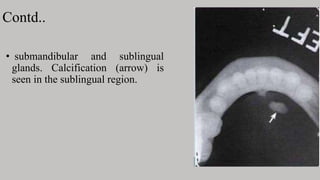

Contd..

• submandibular and sublingual

glands. Calcification (arrow) is

seen in the sublingual region.

Contd.. • submandibular andsublingual glands. Calcification (arrow) is seen in the sublingual region.